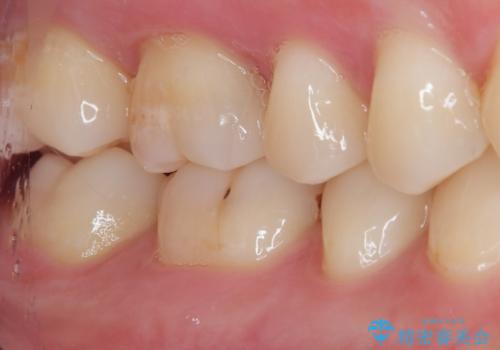

- 数年前他院にて治療した銀歯をやり替え希望の患者様です。

拡大鏡下で、銀歯、むし歯の除去を行い、セラミックインレーに適した形に整えました。